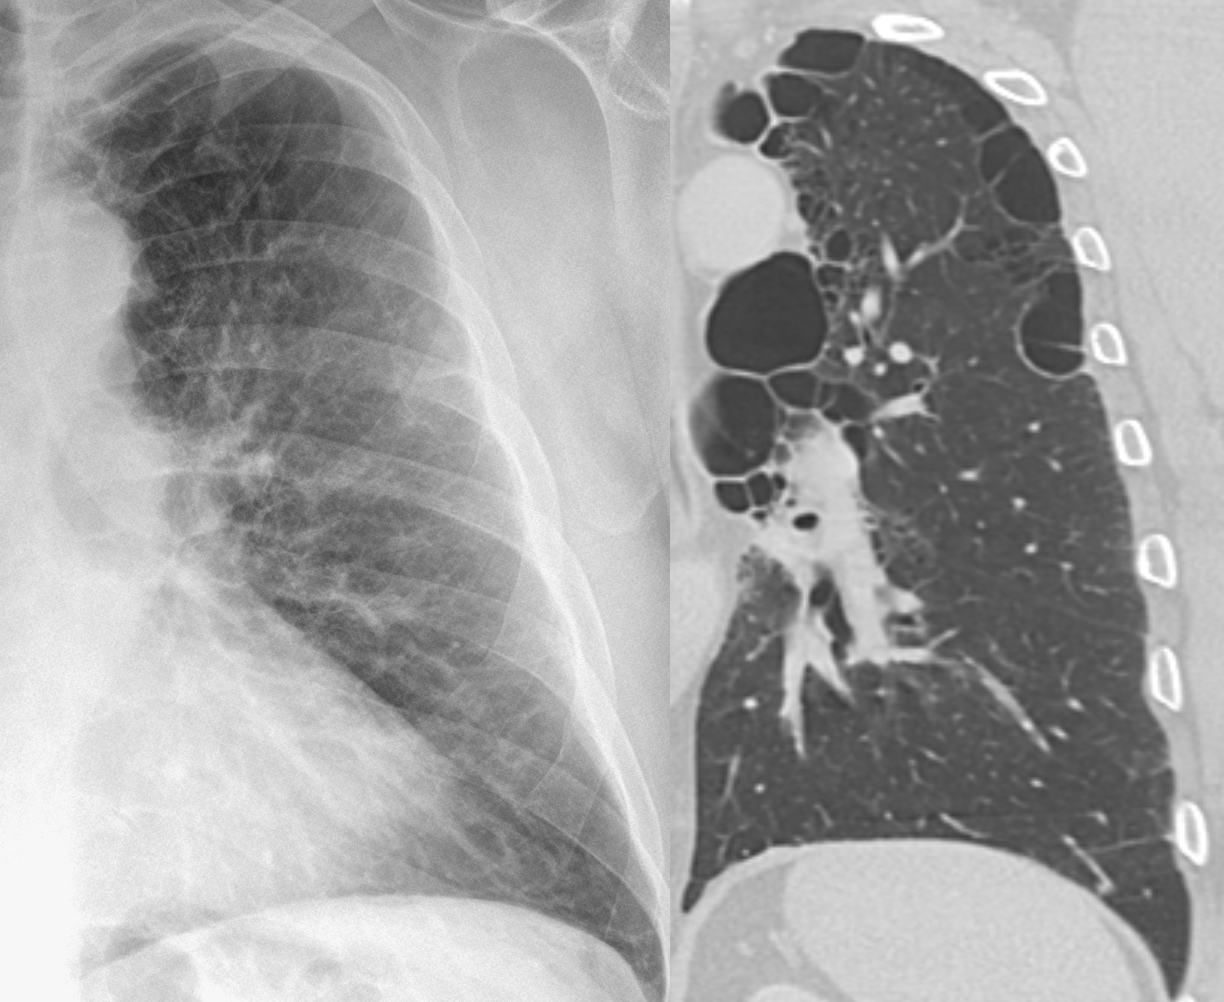

Рентгеновские снимки при врожденной эмфиземе легкого

Раздел: Визуальные уроки